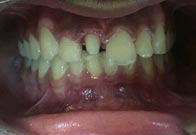

(5) Zirconia Crown

Before Treatment

After Treatment

The patient reported to the clinic with a discoloured upper lateral incisor. X Ray revealed that the tooth was root canal treated.Tooth preparation was done followed by premium zirconia crown thereby restoring the esthetics